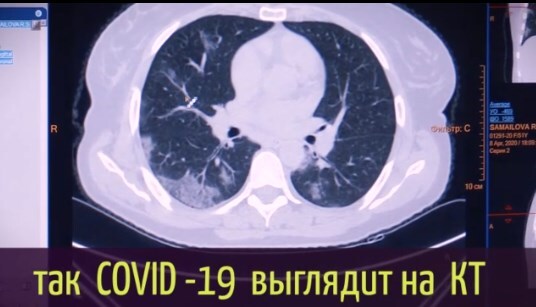

Японские и американские врачи обнаружили патологию у людей, которые переболели коронавирусом без симптомов.

У некоторых пациентов происходят изменения в легких.

Отмечается, что человек чувствует себя нормально, но коронавирус повреждает легочную ткань, на которой образуются уплотнения.

Врач-рентгенолог "Медико-хирургического центра на Пресне" Людмила Леонова пояснила, что воспаленная зона в легких начинает фиброзироваться (фиброз – уплотнение легочной ткани).

По ее словам, если болезнь протекает в легкой форме, то фиброз со временем проходит. Однако в тяжелой форме он чаще всего остается, учитывая возрастные показатели населения.